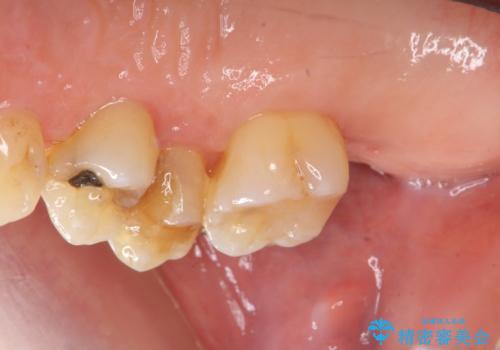

部分矯正を含む 歯周病治療 (再生治療・歯周ポケット除去・MTM・連結補綴)

- 歯のぐらつき、歯周病の検査を希望され来院されました。

検査の結果、強い歯ぎしりによる歯の周囲の骨の吸収が認められたため歯槽骨の再生・歯周ポケットの除去・力に対抗する連結補綴・補綴前処置としての小矯正を計画します。